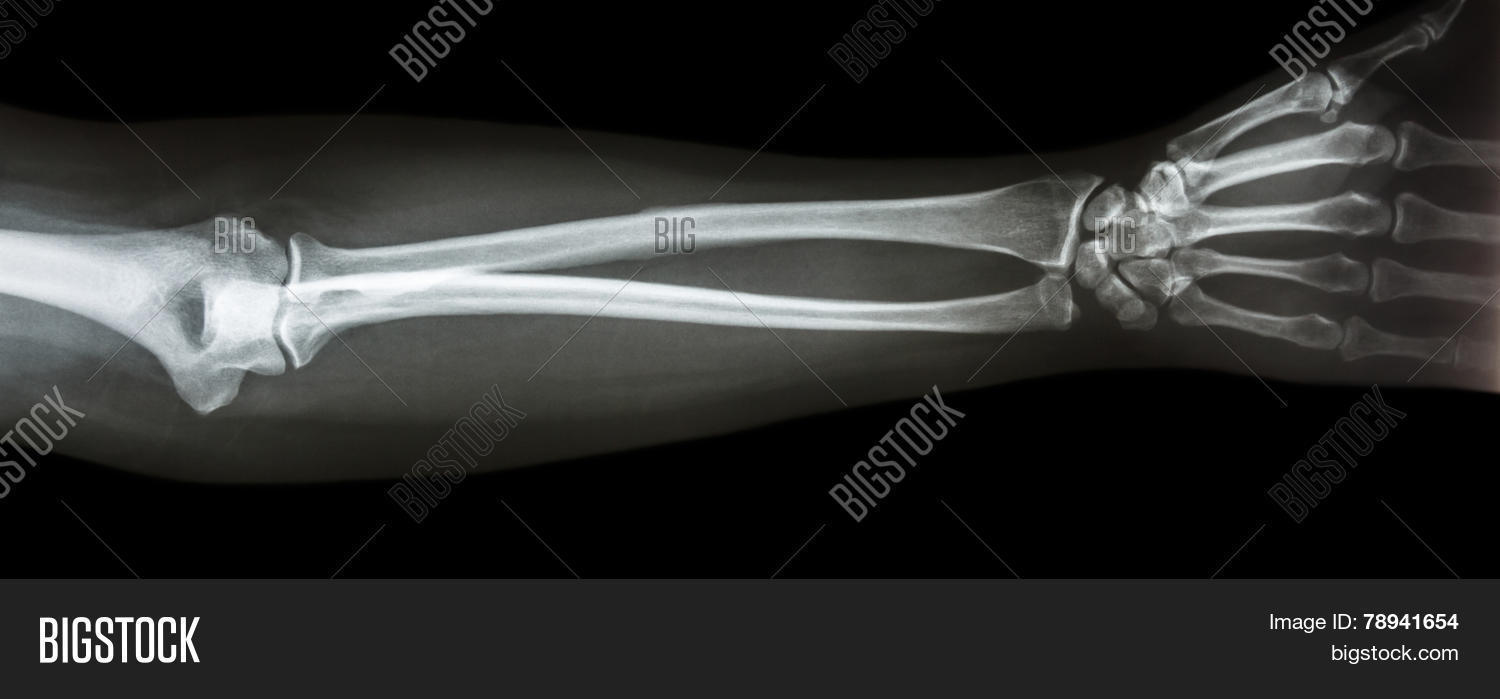

From www.bigstockphoto.com

Film Xray Forearm Ap( Image & Photo (Free Trial) Bigstock Forearm Xray Series ‘this is an ap/lateral/oblique radiograph of the right/left wrist, or scaphoid series.’. Use the many eponyms with caution. forearm fractures are characteristic depending on patient age. In the elderly, osteoporotic fractures of the distal radius are common. Typical fracture patterns arise in the forearm bones depending on mechanism of injury and the age of the patient. at least. Forearm Xray Series.